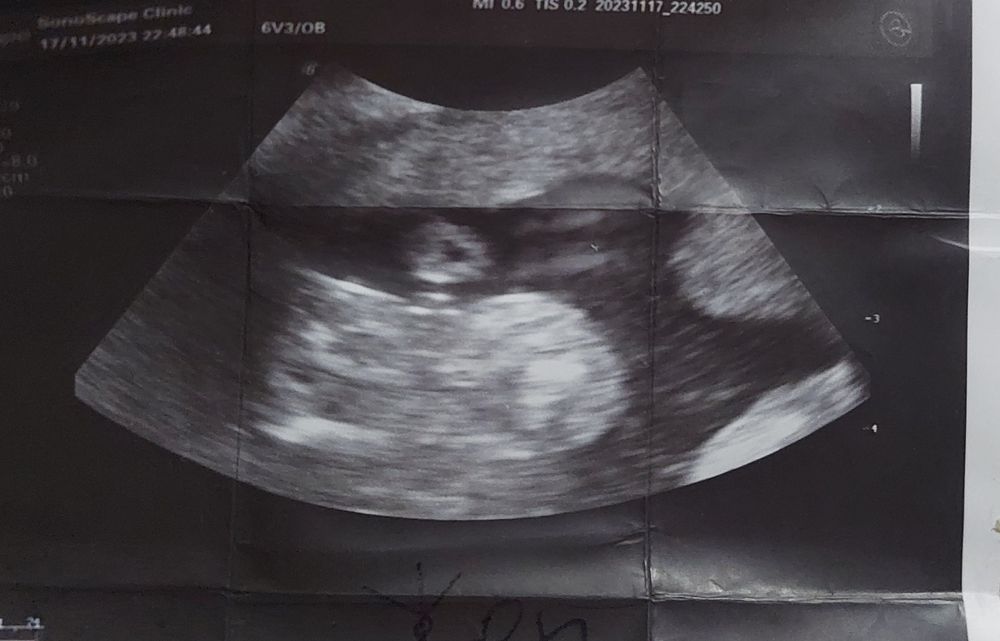

Я бы предположила , что этот кружок сверху это пуповина в разрезе (вижу две артерии и одну Вену)🧐 ну, попало так на снимок ) а вообще, четко видно «кофейное зёрнышко» , так что вероятнее всего - у вас мадам )

Я так понимаю слева попка, а справа это то самое). Так что да, это деваха без сомнений

Хм, похоже, а кружочек сверху это что? Голова виднеется или это простите мошонка?